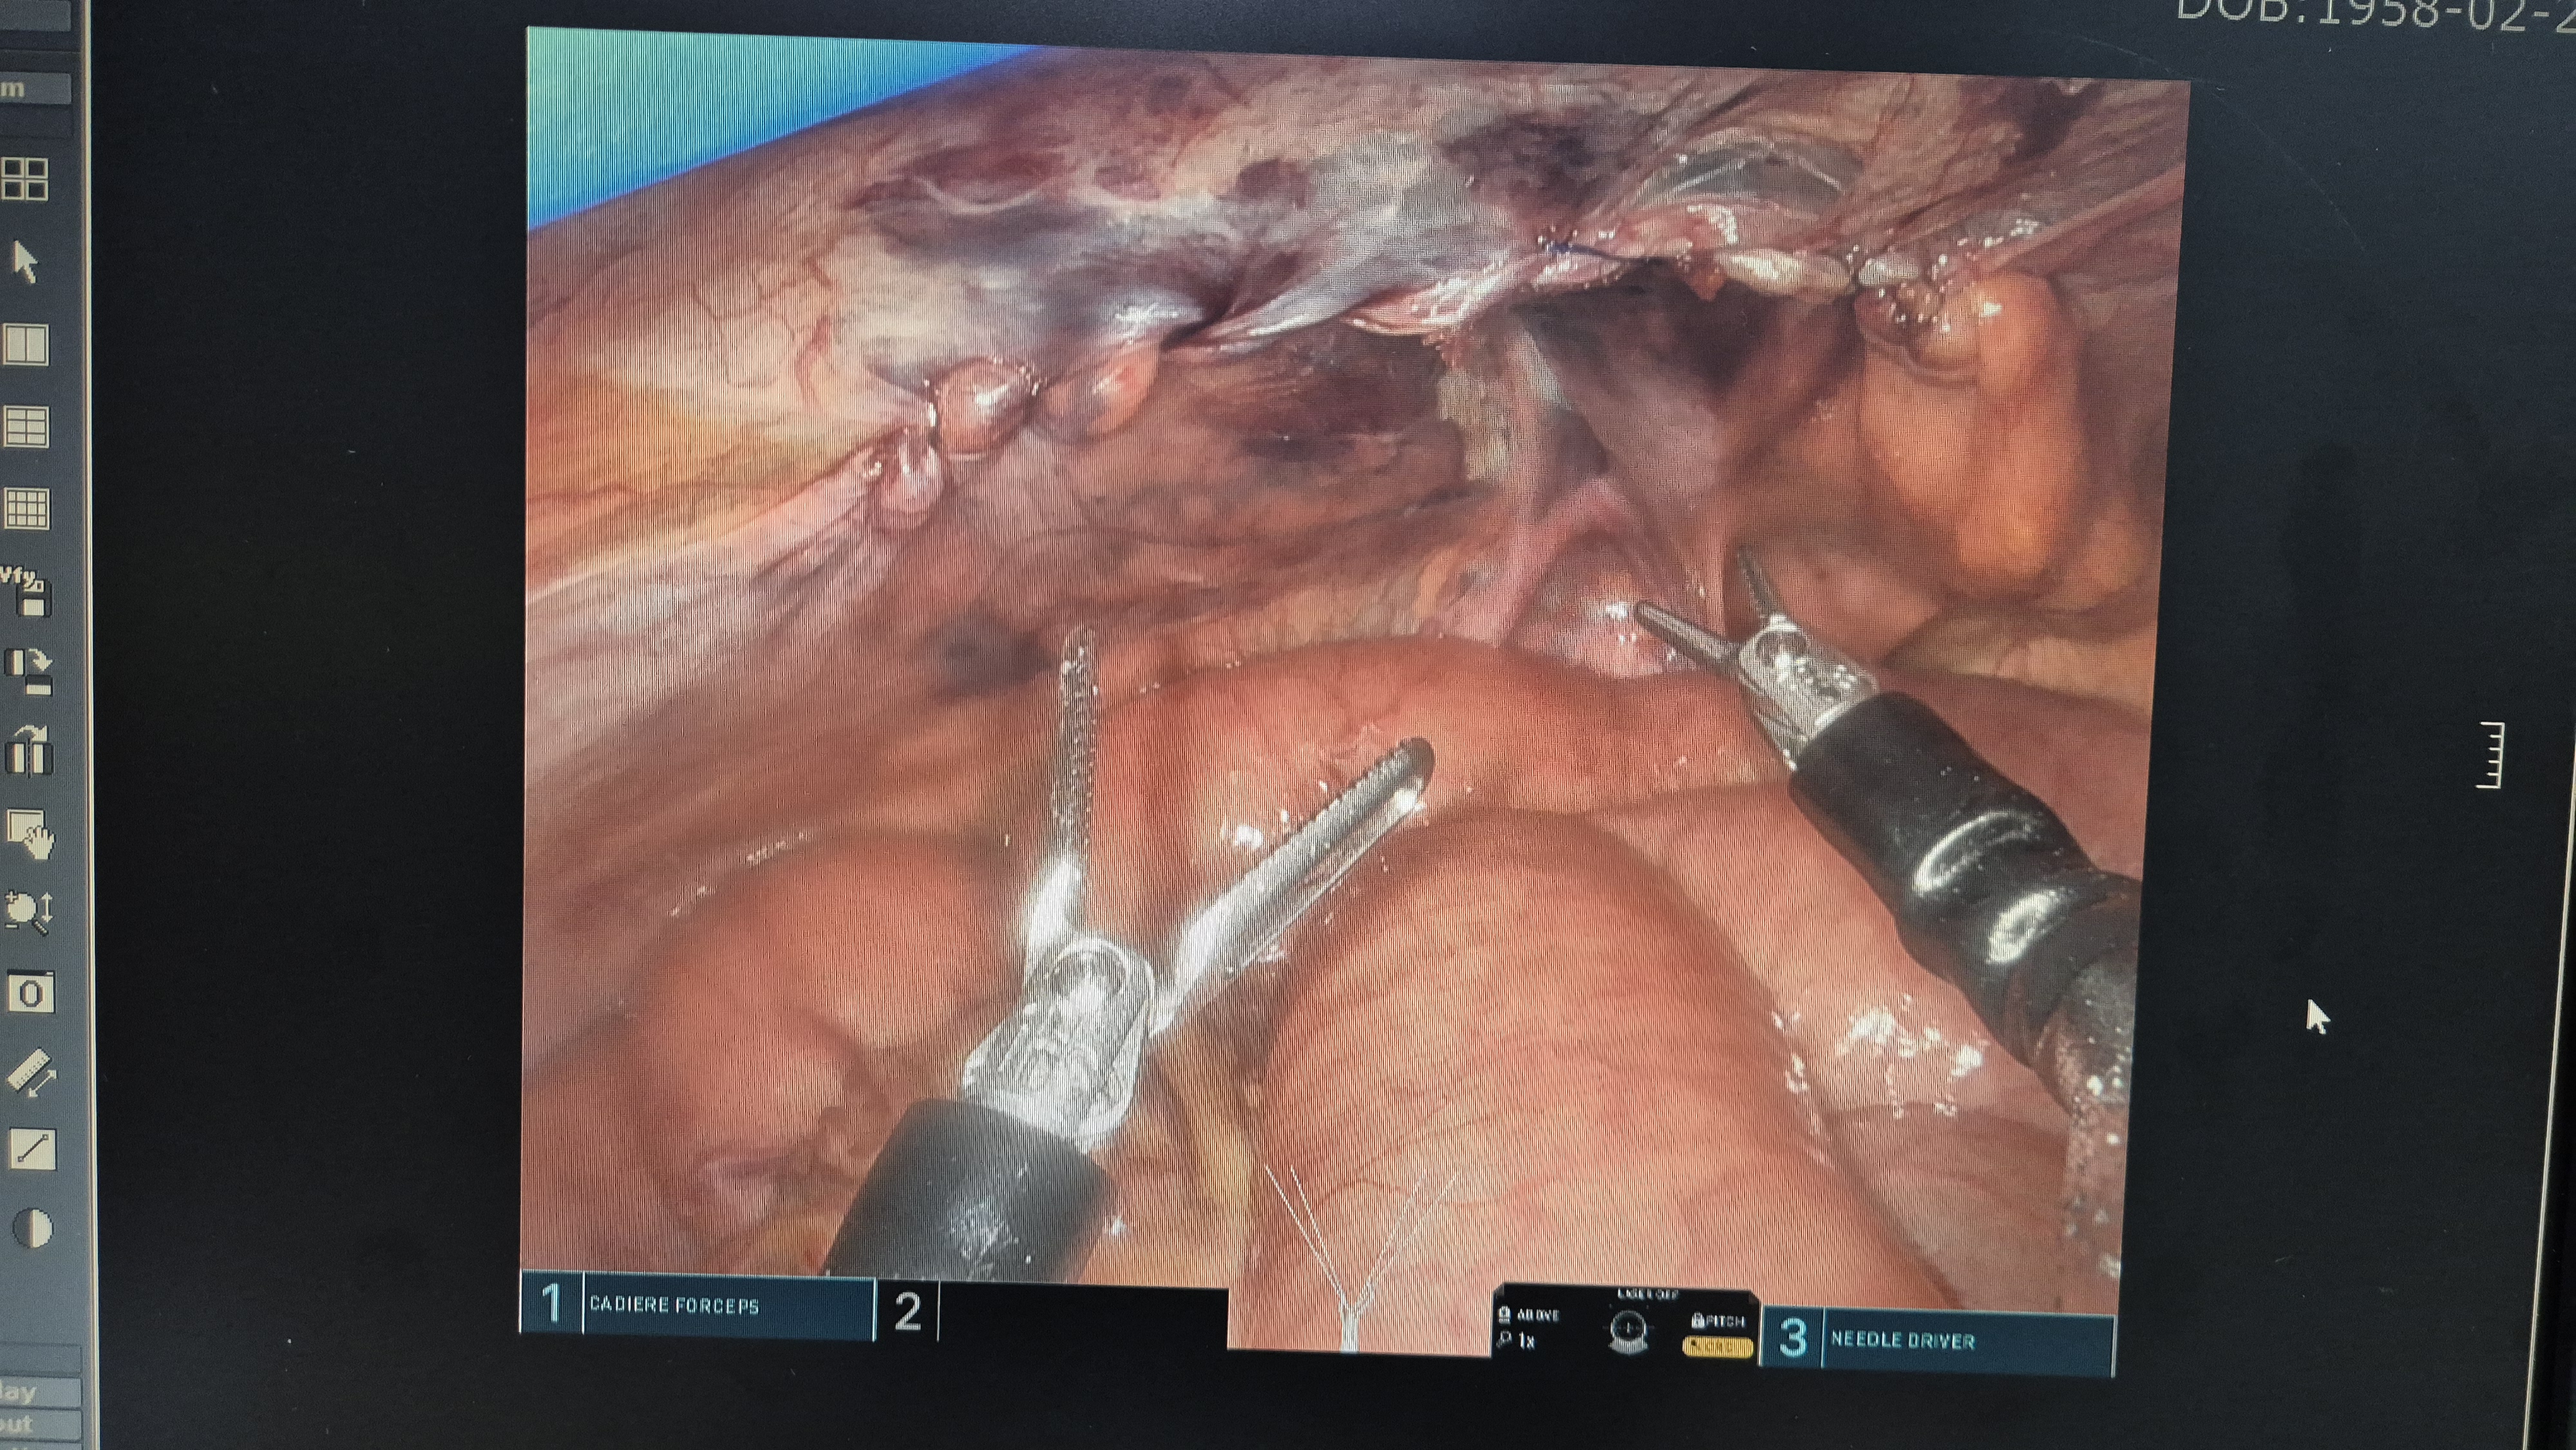

복막 봉합.

복막봉합.